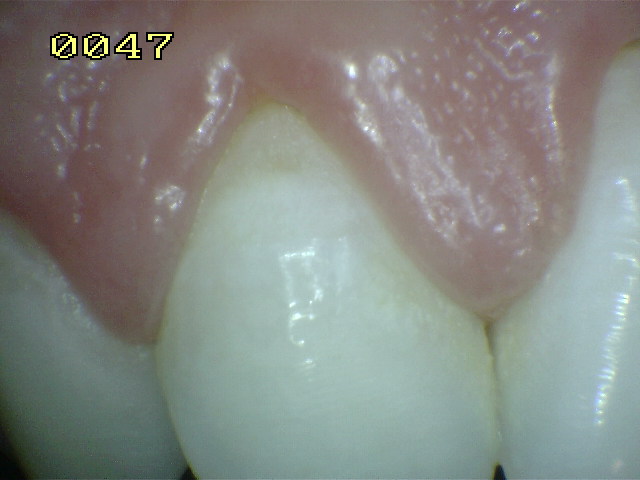

Encía inflamada |

Encía levemente inflamada con un

componente fibroso. Observe el borde gingival con aspecto

liso, turgente y brillante de color rojo |